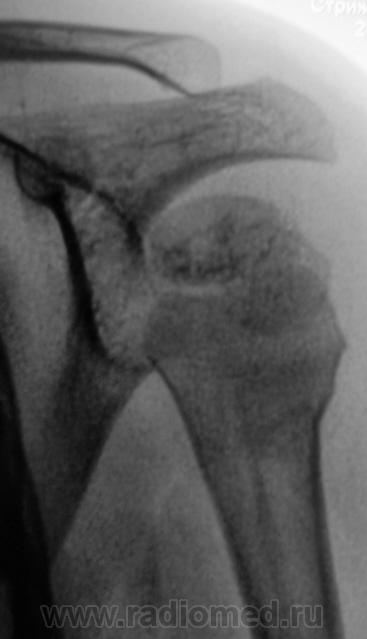

Но у первого пострадавшего помимо перелома и вывиха в плечевом ещё и надрыв/разрыв ключично-акромиального сочленения.

На мой взгляд, вывих спорный.

В обоих случаях перелом хирургической шейки плечевой кости. А почему только в одной проекции? Мы всегда снимаем в двух - в прямой и аксиальной.